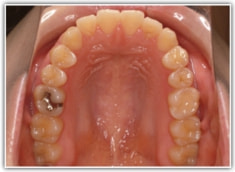

治療前

検査時レントゲンパントモ

現代人には珍しく8番(親知らず)が直立して萌出しています。